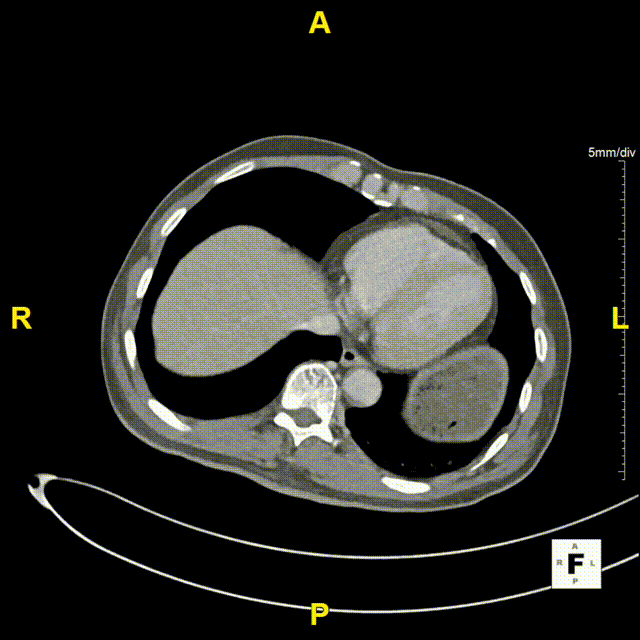

二、术前CTA详解

gore医疗怎么样「漫腹精论」髂合时宜 精益求精——双MOB球囊导管辅助腹主动脉覆膜支架急诊治疗破裂巨大髂动脉瘤_https://www.jmylbn.com_新闻资讯_第5张

gore医疗怎么样「漫腹精论」髂合时宜 精益求精——双MOB球囊导管辅助腹主动脉覆膜支架急诊治疗破裂巨大髂动脉瘤_https://www.jmylbn.com_新闻资讯_第6张

gore医疗怎么样「漫腹精论」髂合时宜 精益求精——双MOB球囊导管辅助腹主动脉覆膜支架急诊治疗破裂巨大髂动脉瘤_https://www.jmylbn.com_新闻资讯_第7张

gore医疗怎么样「漫腹精论」髂合时宜 精益求精——双MOB球囊导管辅助腹主动脉覆膜支架急诊治疗破裂巨大髂动脉瘤_https://www.jmylbn.com_新闻资讯_第8张

gore医疗怎么样「漫腹精论」髂合时宜 精益求精——双MOB球囊导管辅助腹主动脉覆膜支架急诊治疗破裂巨大髂动脉瘤_https://www.jmylbn.com_新闻资讯_第9张

gore医疗怎么样「漫腹精论」髂合时宜 精益求精——双MOB球囊导管辅助腹主动脉覆膜支架急诊治疗破裂巨大髂动脉瘤_https://www.jmylbn.com_新闻资讯_第10张

gore医疗怎么样「漫腹精论」髂合时宜 精益求精——双MOB球囊导管辅助腹主动脉覆膜支架急诊治疗破裂巨大髂动脉瘤_https://www.jmylbn.com_新闻资讯_第11张